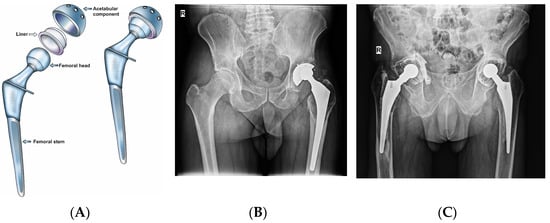

- Thejeel, B.; Endo, Y. Imaging of Total Hip Arthroplasty: Part I—Implant Design, Imaging Techniques, and Imaging of Component Wear and Fracture. Clin. Imaging 2023, 98, 74–85. [Google Scholar] [CrossRef]